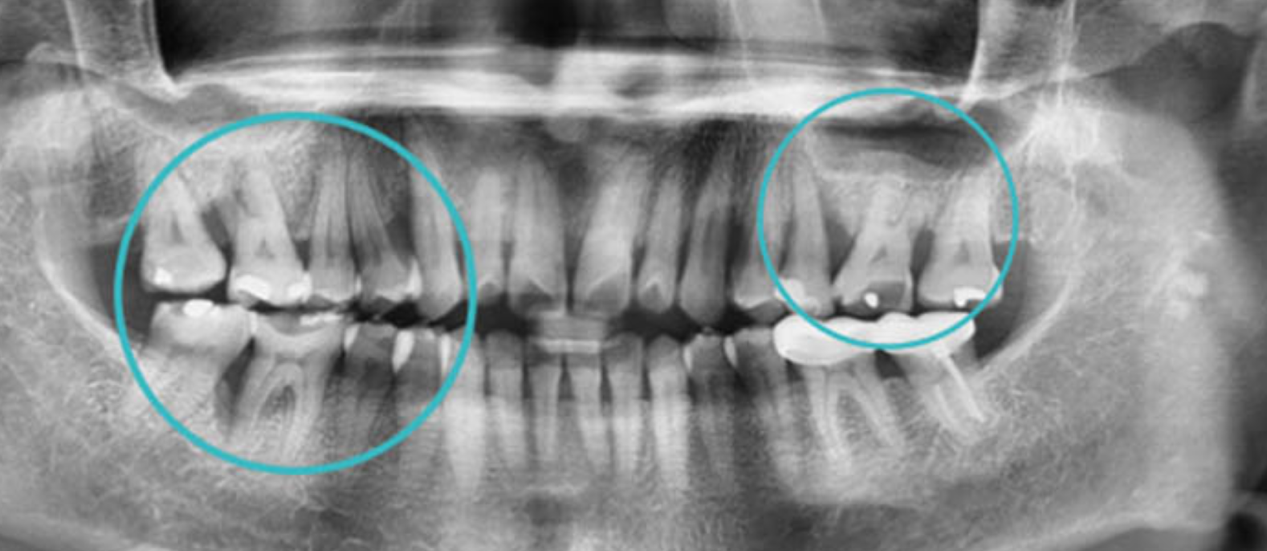

1名年僅33歲的女性上班族正是典型案例,鄭聖達醫師指出,該患者在其他診所診斷出牙周病後,轉診前來治療,個案並無吸菸、糖尿病或服用特殊藥物等風險因素,經檢查發現,她的幾顆牙齒齒槽骨遭到牙周病破壞得特別嚴重,感到牙齒痠軟、晃動。

▲經檢查發現該女性上班族幾顆牙齒齒槽骨遭到牙周病破壞得特別嚴重。(圖/鄭聖達醫師提供)

鄭聖達醫師進一步說明,原先針對該病患使用牙周探針在每顆牙齒裡外6個面進行深度測量,已遭到破壞的數顆牙齒深度高達10mm之多,比正常範圍還再嚴重破壞5mm深度。